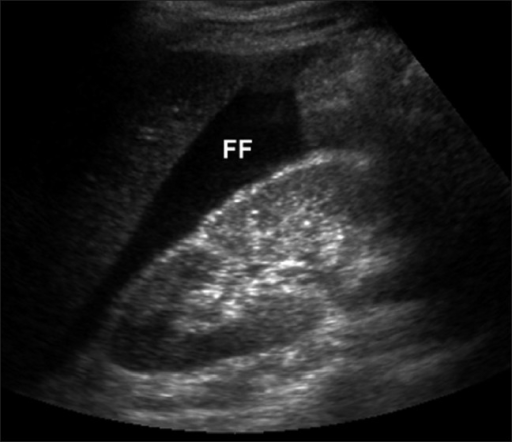

Positive FAST

(Acquired from: OPENi - An Open Access Biomedical Search EngineAn Open Access Biomedical Image Search Engine)